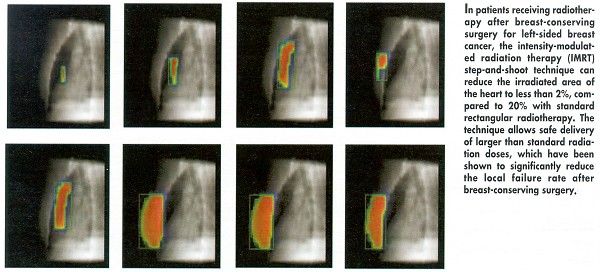

However, the danger of long-term cardiac complications can be largely overcome with the new technique known as intensity-modulated radiation therapy (IMRT). With IMRT, radiotherapists use multileaf collimators to divide one wide beam into many smaller beam segments, or bixels. They can then individually determine the intensity of each bixel and deliver high-dose radiation to the precise spot where it is needed, while sparing critical normal tissue.

Dr. Bartelink explained that, during standard rectangular radiotherapy for left-sided breast cancer, as much as 20% of the myocardium is irradiated. In contrast, he noted, with IMRT, less than 2% of the myocardial tissue is exposed to radiation.

Dr. Bartelink and his Netherlands Cancer Institute colleagues have found that using the IMRT "step-and-shoot" technique to avoid the heart can reduce the risk of myocardial infarction to less than 1%, down from 7% with standard radiotherapy and 3% with three-dimensional conformal radiotherapy.